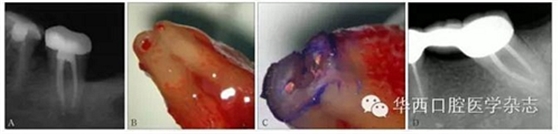

A:42牙術(shù)前X線根尖片示根充至距影像學(xué)根尖0.5~1 mm內(nèi);B:顯微外科根尖手術(shù)術(shù)中切除根尖,體視顯微鏡 × 40。藍(lán)色箭頭示根尖段根管內(nèi)殘留壞死牙髓組織及感染物質(zhì),黑色虛線示根尖段根管,紅色箭頭示原牙膠充填止點(diǎn)。

圖4 X線根尖片未準(zhǔn)確指示根管工作長度

A:37牙術(shù)前X線根尖片示根充至距影像學(xué)根尖0.5~1 mm;B:37牙行意向性牙再植術(shù),拔出后可見根尖牙膠超填,解剖學(xué)根尖孔距解剖學(xué)根尖有一定距離;C:截取根尖3 mm,甲苯胺藍(lán)染色示C型根管;D:47牙根管治療10年回訪,X線根尖片顯示,雖充填物距離影像學(xué)根尖約3 mm,但愈后良好。

圖5 X線根尖片評估復(fù)雜根管系統(tǒng)根管工作長度存在局限性